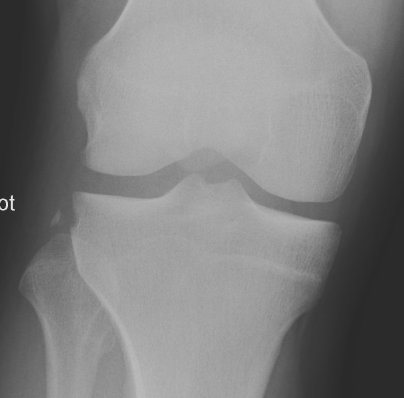

Segond Fracture

This is a very subtle "avulsion fracture of the tibia below the articular margin" caused by traction on the capsular or coronary ligaments. It is not possible to cause this fracture without first rupturing at least one of the major ligaments in the knee.

The classical description1 is limited to the lateral side where associated injuries include:-

Examples in order of increasing subtlety: -